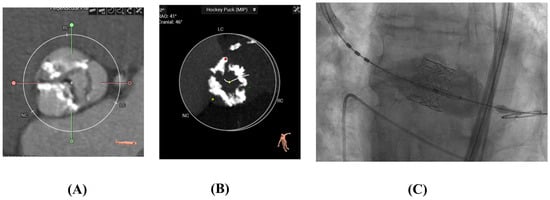

2.4. Transcatheter Aortic Valve Replacement

Transcatheter aortic valve replacement (TAVR) is a minimally invasive procedure developed as an alternative to SAVR, particularly for patients with symptomatic severe aortic stenosis. Rather than excising the native valve leaflets, TAVR involves delivering a bioprosthetic valve via a catheter, most commonly through transfemoral arterial access, although alternative access routes (e.g., transapical, transaortic, trans-carotid) may be used when necessary (Figure 4). The prosthetic valve—typically mounted on a balloon-expandable or self-expanding stent frame—is positioned within the diseased calcified native aortic valve. Upon deployment, the native leaflets are displaced outward by expanding the stent frame and anchoring the new valve in the native annulus, allowing it to assume the function of the native valve. This technique obviates the need for sternotomy, thoracotomy, or cardiopulmonary bypass. Since its first human implantation in 2002, TAVR has undergone rapid technological evolution and is now used across a broad spectrum of surgical risk profiles, including intermediate- and low-risk patients, with ongoing studies exploring its application in younger populations with less severe aortic stenosis and even aortic regurgitation.

Figure 4. (A,B) CT scans of calcified aortic valves pre-TAVR (C). Edwards-Sapien TAVR Valve Deployed.